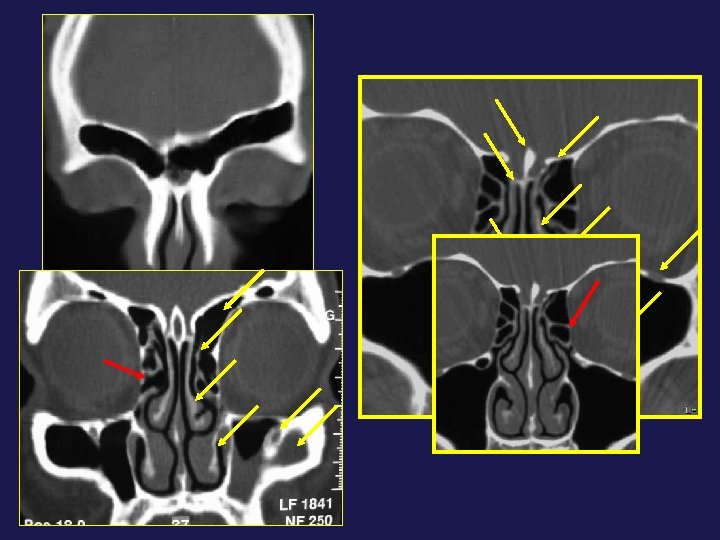

→ Hémorragie : lésion artère éthmoïdale antérieure

→ Orbite : hématome

→ Hémorragie